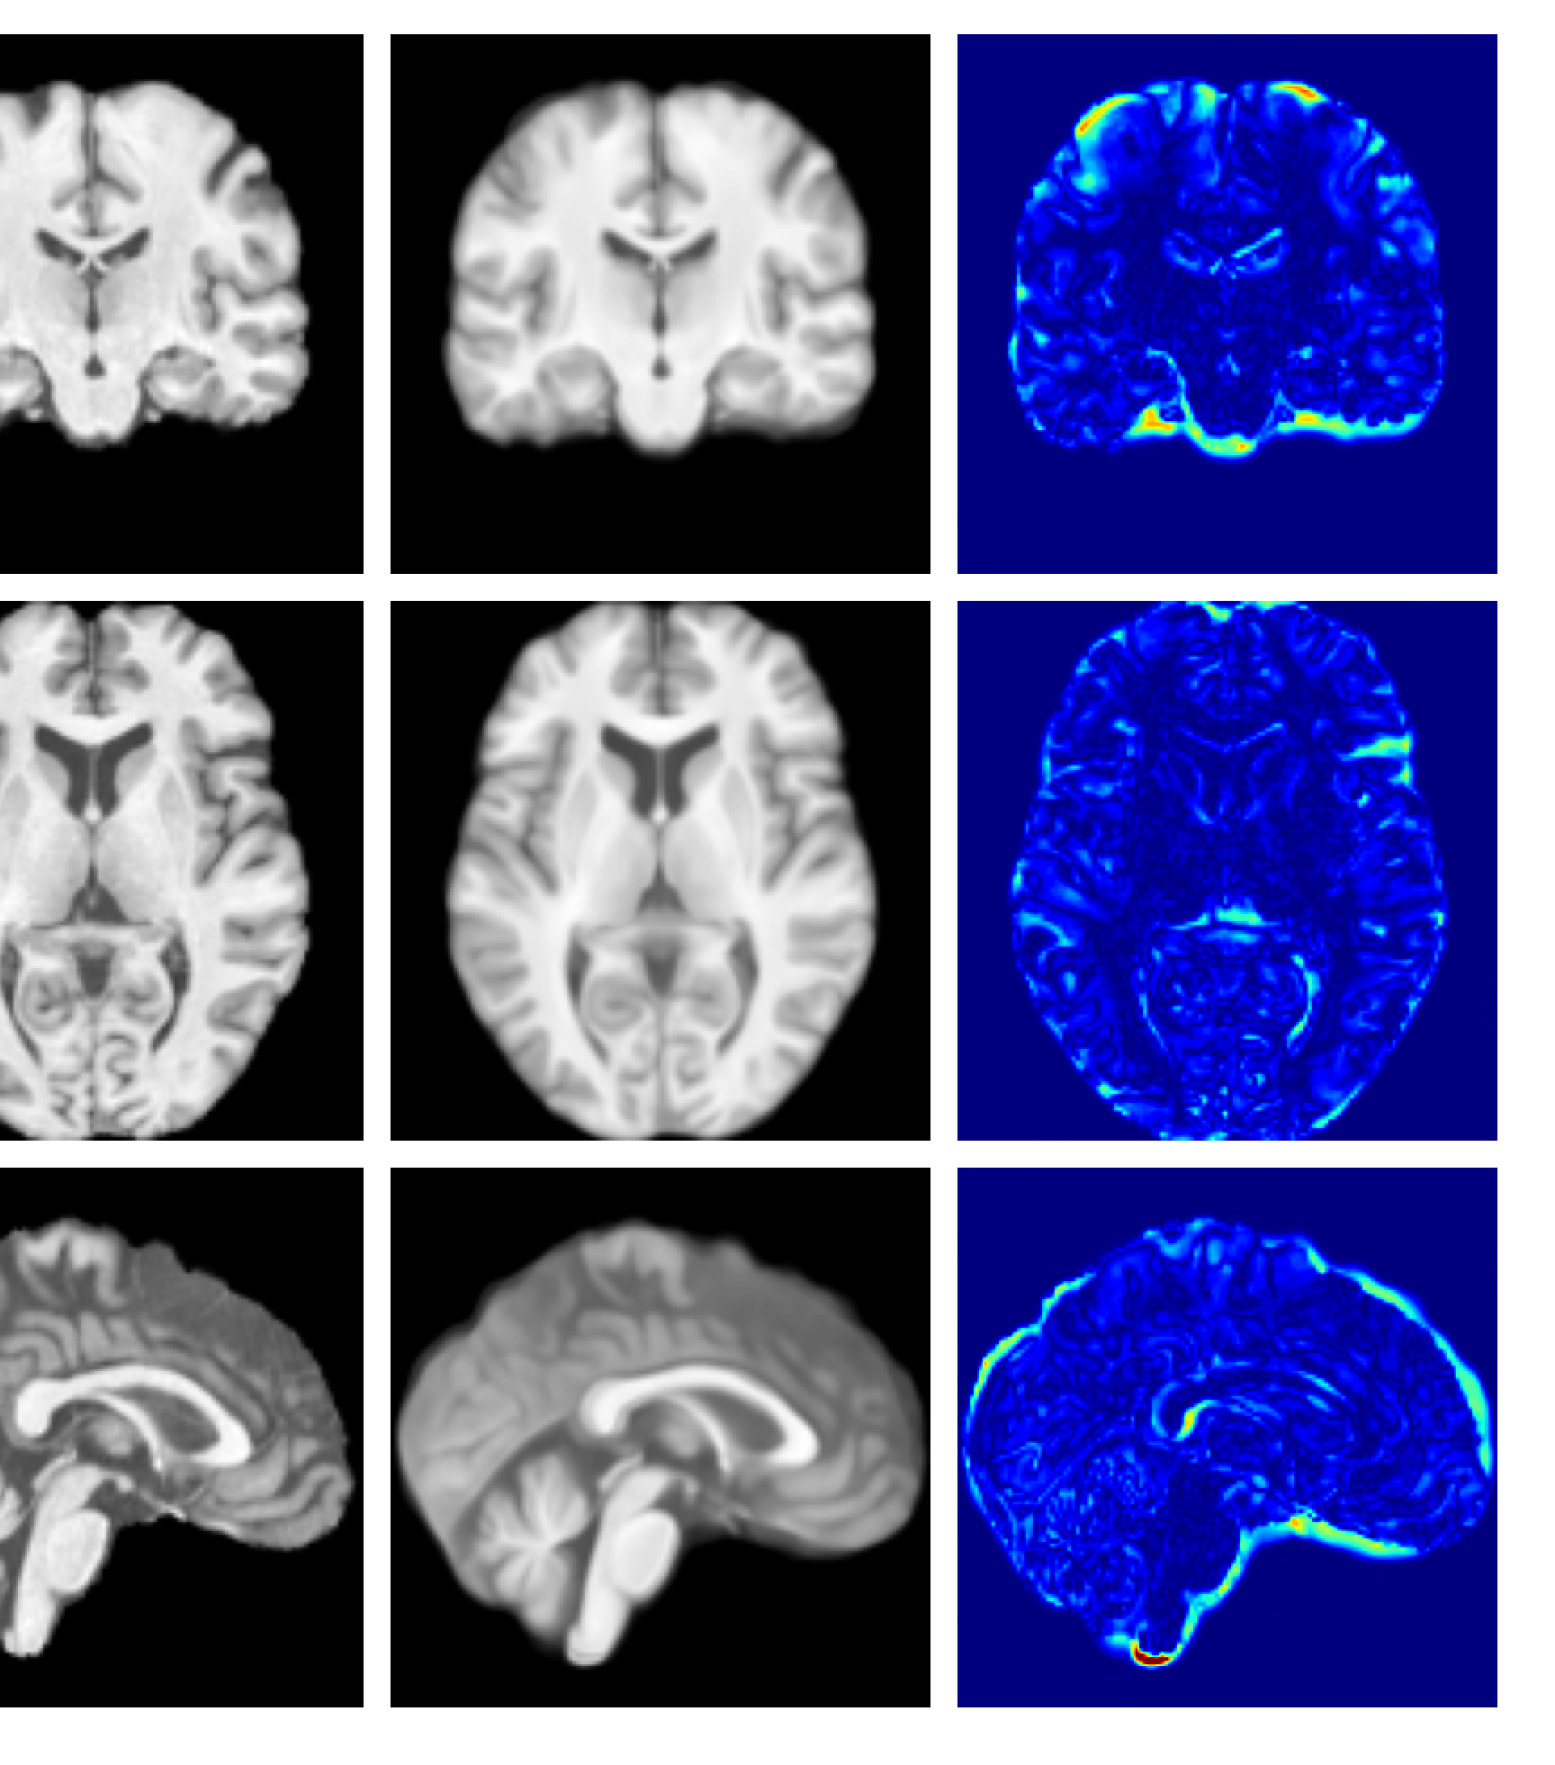

Figure 7 provides example reconstructions and anomaly maps for a healthy subject from the UK Biobank holdout test cohort.

Figure 7: Example healthy reconstructions and anomaly maps for a sample from the UK Biobank healthy test cohort. For a healthy subject, we should observe no regions highlighted in the anomaly map.